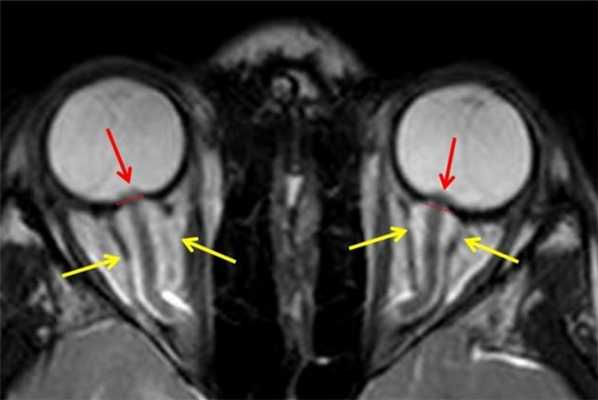

МРТ орбит. На МРТ орбит в аксиальной плоскости отмечается минимально выраженный отек ретробульбарной клетчатки с наличием жидкостного содержимого (желтые стрелки) вдоль зрительных нервов (расширение субарахноидального пространства), приводящие к масс-эффекту зрительных нервов (красные стрелки) и деформации глазного яблока.